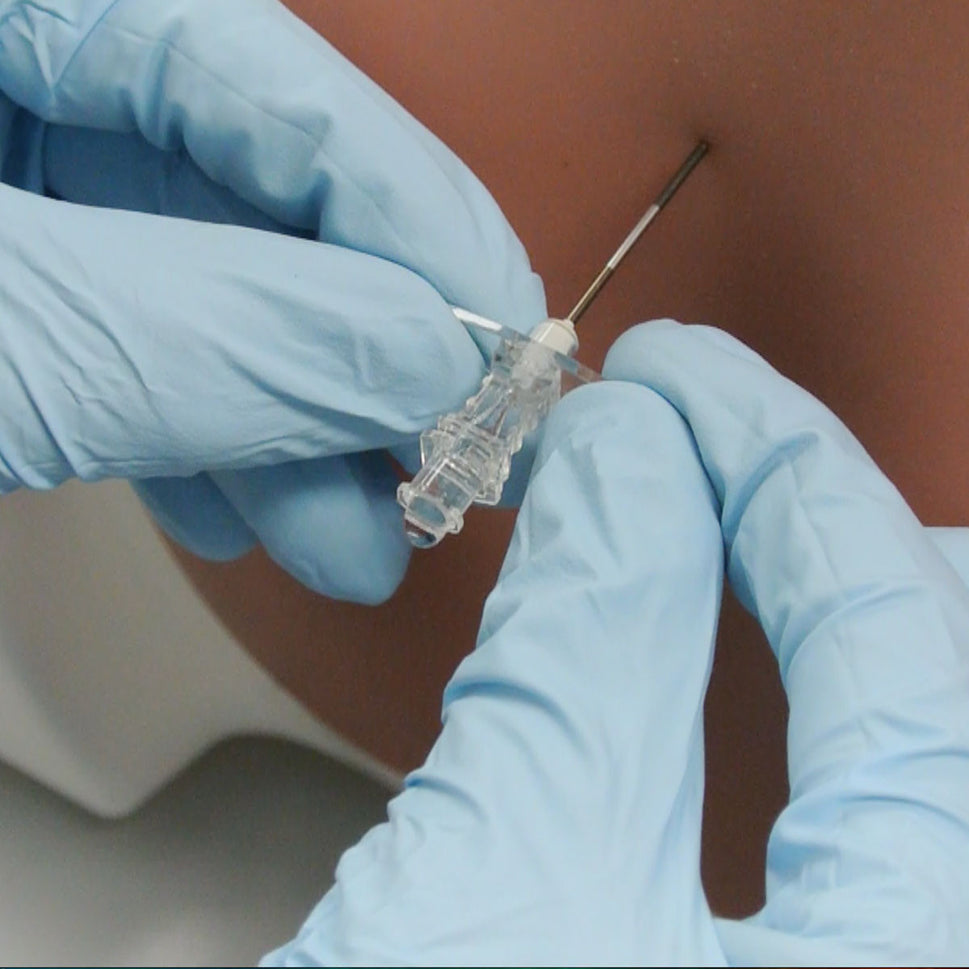

Train students and healthcare professionals in essential epidural injection skills using our highly realistic spine simulators, designed to enhance clinical training and procedural accuracy.

Our range of epidural injection trainers includes detailed anatomical models that replicate the lumbar and thoracic spine, providing a hands-on learning experience for anaesthetists, medical students, and pain management specialists. These advanced simulators allow users to practise needle placement, identify key anatomical landmarks, and develop proficiency in administering epidural and spinal anaesthesia with confidence. Ideal for medical schools, hospitals, and professional training programmes, these epidural trainers support skill development in regional anaesthesia, labour pain management, and spinal procedures. With lifelike materials that simulate real patient responses, our models offer a realistic and immersive training experience.